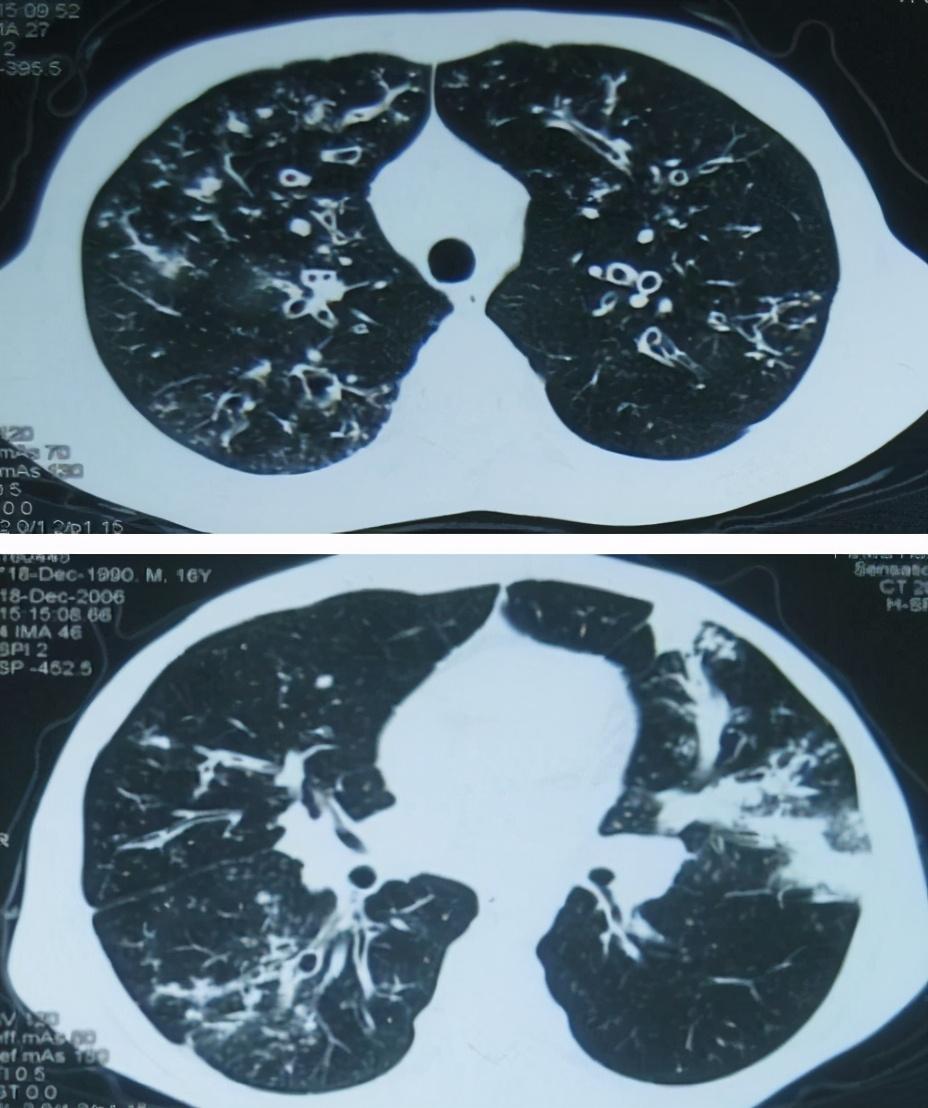

摘要:关于支气管扩张症的最新研究正在不断深入,为临床治疗提供了新的思路和方法。研究内容包括病理机制、诊断技术、治疗方案等方面的探索。步骤指南包括从研究准备、实验设计、数据分析到成果总结的完整流程。这些研究为支气管扩张症的治疗提供了有力支持,有望帮助患者获得更好的疗效和生活质量。

在阅读最新研究进展之前,首先需要了解支气管扩张症的基础知识,包括定义、症状、诊断和治疗方法等。